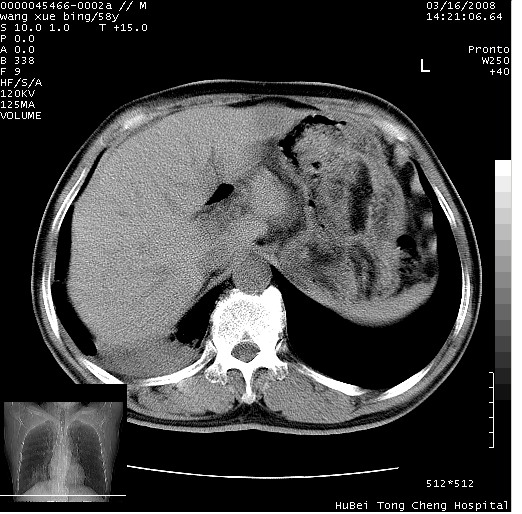

胸部ct轴位平扫(层厚10mm,螺距1.5,重建间隔10mm),图像如下:

右肺下叶团块及不规则空洞,内壁不规则,外缘见粗长毛刺,临近胸膜明显增厚并与病灶关系密切。支持考虑:右肺肺脓肿!建议穿刺病理检查待除外周围型肺癌!

考虑右下肺周围型肺癌并远端阻塞性炎症及胸膜转移

考虑右下肺中心型肺癌并远端阻塞性炎症及胸膜及纵隔淋巴转移

空洞壁厚,不规则,其内可见壁结节,周围可见毛刺及阻塞性炎变,多考虑癌性病变.

支持癌性空洞并远端阻塞性炎症